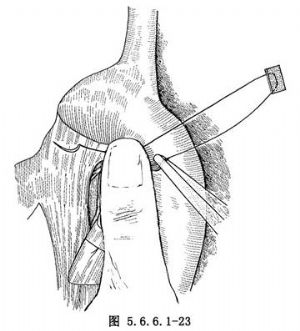

如肿瘤位置较高不能作弓下吻合,应作主动脉弓上吻合,需要将食管继续向上游离。在主动脉弓下缘常有1~2支直接来源于主动脉的食管固有动脉供应食管,要仔细分出,用丝线结扎后切断,不能贸然剪断,否则将造成危险的大出血(图5.6.6.1-21)。一旦固有动脉被损伤,切记不可用止血钳乱夹,术者可用右手示指尖按压出血处(图5.6.6.1-22)。然后用无损伤针及2/0号涤纶线携带一个1cm×1.5cm大的涤纶补片,由按压出血处的示指端右缘进针,由指端左缘出针,用缝线另一端的针由距离前一针0.6cm处的下方再缝一针(图5.6.6.1-23)。两根针再次穿过另一块补片(图5.6.6.1-24)。抽出按压出血处的手指,结扎涤纶线(图5.6.6.1-25)。每个缝线打结6次,如仍有小渗血可补缝数针。正确处理食管在主动脉弓下的固有动脉的方法为由主动脉弓下缘仔细解剖,找出血管后结扎,或切开主动脉弓上缘的纵隔胸膜,用手指由主动脉弓后方、食管前壁与主动脉弓之间轻轻向下外方向顶,即可将固有动脉由弓下显露。如固有动脉位置较深,可用手指尖端由主动脉下方,食管前壁与主动脉弓之间轻轻向上顶,即可将固有动脉由弓上显露(图5.6.6.1-26)。将固有动脉处理完后,即可将已在贲门处切断的食管由主动脉后方提至弓前方作吻合(图5.6.6.1-27)。